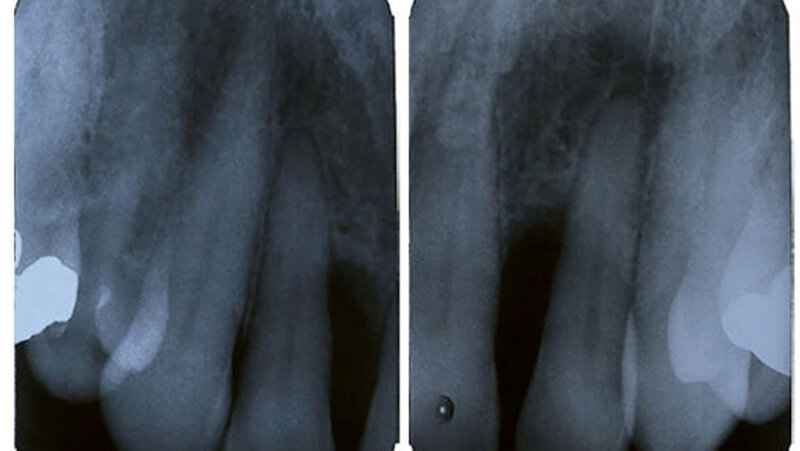

Eine 61-jährige Patientin mit einer postmenopausalen Osteoporose, einer Divertikulose, seit 2005 bekannten und im Verlauf größenregredienten Pankreaszysten sowie einer Allergie auf Neo-Citran® stellte sich aufgrund einer zwar relativ lokalisierten, gleichwohl aber schweren Parodontitis vor. Insbesondere die lateralen Inzisiven zeigten dabei Sondierungstiefen bis zu 9mm mit Suppuration/Bluten auf Sondieren (Abbildung 1 und 2), die bisher – trotz relativ guter Mundhygiene – bei verschiedenen Zahnärzten ohne Erfolg behandelt wurde.

Diese Befunde waren mit entzündlichen Veränderungen und somit mit der klinischen Präsentation und den Laborbefunden vereinbar. Aufgrund dieser Befunde wurde die Patientin auf der gastroenterologischen/viszeralchirurgischen Station des Inselspitals Bern zur weiteren Behandlung stationär aufgenommen. Unter Hydrierung, analgetischer Therapie sowie Nahrungskarenz stellte sich in der Folge eine Besserung ein und die Patientin konnte nach drei Tagen in gutem Allgemeinzustand nach Hause entlassen werden. Zahnmedizinisch zeigten die weiteren Recalls nach Initialtherapie erfreuliche parodontale Befunde, weshalb keine weiteren parodontalchirurgischen Therapien durchgeführt werden mussten (Abbildung 1 und 2).